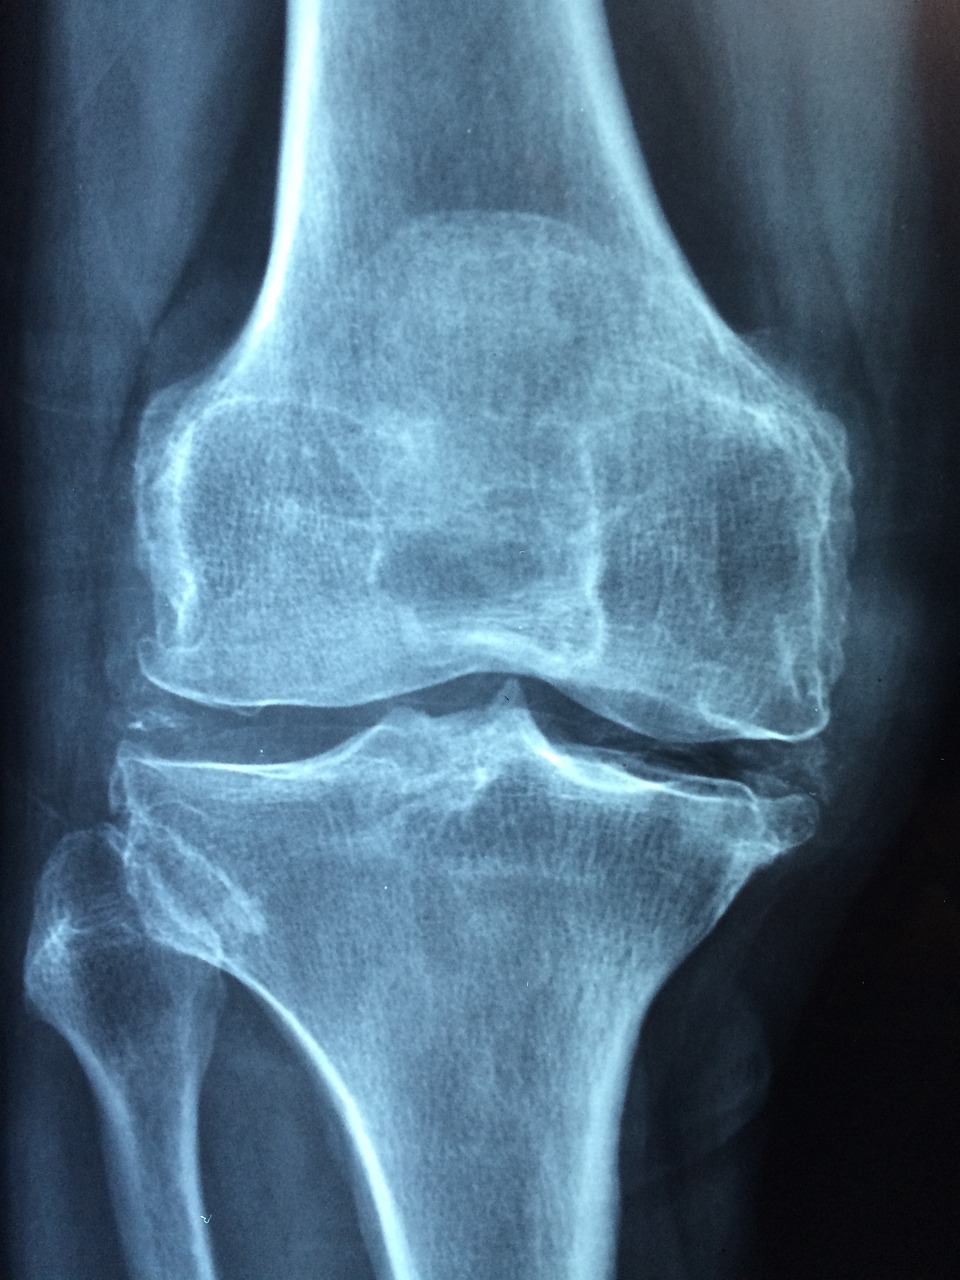

골다공증을 진단하는 가장 일반적인 방법은 **이중 에너지 X선 흡수계(DXA)**를 이용하는 것입니다. 이 테스트는 골밀도를 측정하고 골다공증이 있는지 확인하기 위한 T-점수를 제공합니다.

1) T-점수 기준

- 보통: -1.0 이상

- 골감소증: -1.0 ~ -2.5(골량은 낮지만 골다공증은 아님)

- 골다공증: -2.5 이하(상당한 뼈 손실을 나타냄)